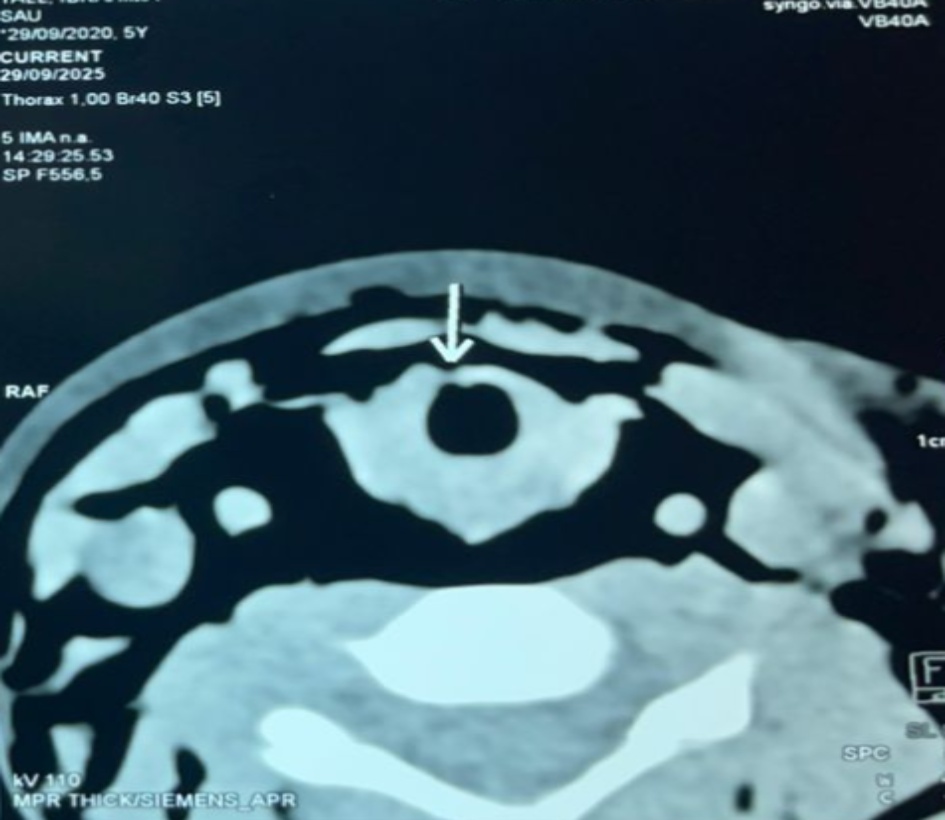

The cervicothoracic CT scan revealed an anterior tracheal breach of 2 mm at the level of the C5 vertebral body, complicated by diffuse cervicothoracic emphysema, a moderate pneumomediastinum, and a small bilateral pneumothorax, without any cartilage injury or associated fracture (Figure 2).

Figure 2. Cervical CT scan showing an anterior tracheal breach of about 2 mm with diffuse cervical emphysema.